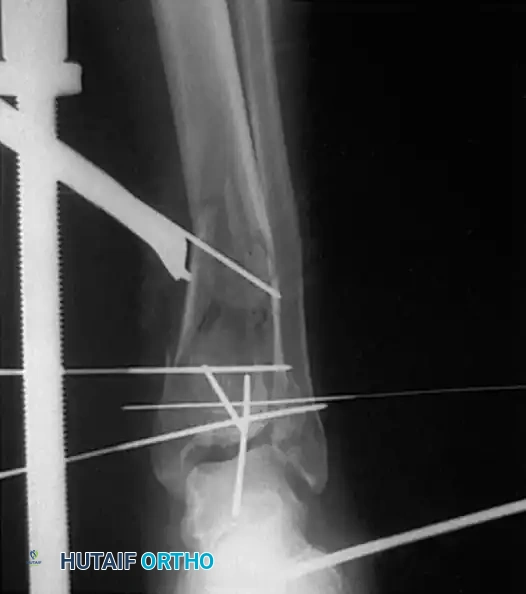

Complex Fracture Patterns and External Fixation

In cases of severe soft-tissue compromise (e.g., fracture blisters, massive edema, or open fractures), immediate internal fixation is contraindicated due to the high risk of wound dehiscence and deep infection.

In these scenarios, damage-control orthopedics is employed. A spanning external fixator is applied to restore length, alignment, and rotation while allowing the soft-tissue envelope to recover.

Once the "wrinkle sign" appears (typically 7 to 14 days post-injury), indicating resolution of edema, the patient is returned to the operating room for definitive ORIF.